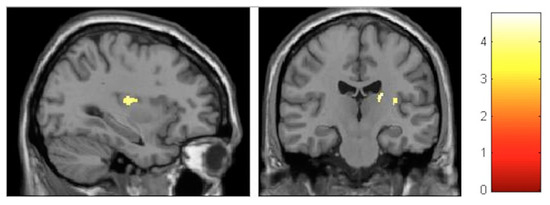

| Effect | Brain Region | Left Hemisphere MNI Coordinates (Cluster Size in Voxels) | T | d | Right Hemisphere MNI Coordinates (Cluster Size in Voxels) | T | d |

|---|---|---|---|---|---|---|---|

| Increment | Paracentral | −9, −32, 59 (1298) | 5.93 | 0.41 | 14, −36, 63 (1589) | 5.47 | 0.40 |

| Increment | Hippocampus | 34, −16, −11.5 (20) | 3.85 | 0.36 | |||

| Decrement | Insula | −32, −10, 12 (60) | 3.91 | 0.36 | 35, −20, 18 (261) | 4.36 | 0.38 |

| Decrement | Putamen | −20, 14, 0 (1879) | 5.45 | 0.40 | 24, 11, 2 (137) | 4.13 | 0.37 |

| Decrement | Cerebellum | −12, −47, −21 (511) | 5.33 | 0.40 | 11, −47, −23 (262) | 4.06 | 0.37 |